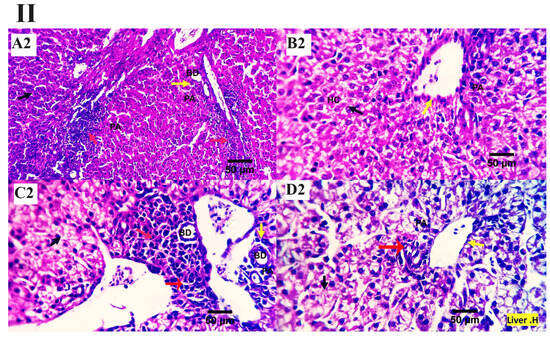

The inspected liver sections from the various treated groups (0, 200, 400, 600 mg MMUR kg−1) show typical histological characteristics of various structures, including portal area and hepatocytes, which are seen as small masses around the central veins. Several round cells were observed around the hepatic portal area, indicating a natural immune response (Figure 1). Mild to moderate portal lymphoplasmacytic aggregations and biliary proliferation were seen in the control group (Figure 1A). Mildly aggregated immune-responsive lymphoplasmacytic cells were observed for MMUR at levels 400 and 600 mg kg−1 (Figure 1C,D). The aggregated inflammatory cells appear to be an immune surveillance and protective device instead of a destructive inflammatory procedure (Figure 1).

Figure 1.

(I,II) Photomicrographs from the liver ((I): H&E × 100 magnification, (II): H&E × 400 magnification) of various chicken experimental groups, which received 0 mg/kg MMUR (A1,A2), 200 mg/kg MMUR (B1,B2), 400 mg/kg MMUR (C1,C2), and 600 mg/kg MMUR (D1,D2). These show typical histological characteristics of various structures, including portal area (PA, yellow arrow) and hepatocytes (HC, black arrow), which are seen as a small masses around the central veins (CV), with a few round cells observed around the portal area indicating a natural immune response. Mild to moderate portal lymphoplasmacytic aggregations (red arrows) and biliary proliferations (BD, yellow arrow) are detected in group (A). Mildly aggregated immune-responsive lymphoplasmacytic cells can be observed in groups (C,D) (red arrows).